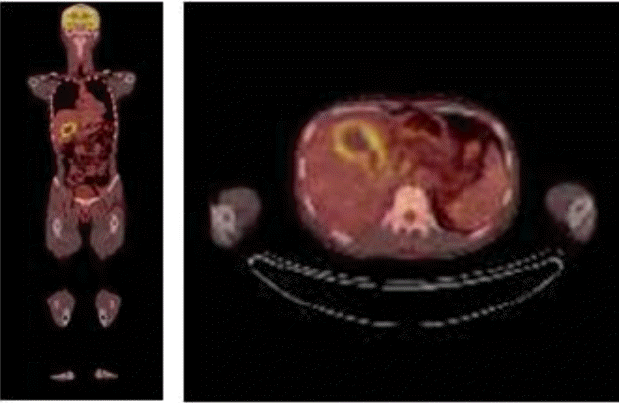

Figure 1.

Computed tomography at another hospital showed no hepatobiliary tract abnormalities or gall bladder wall edema.